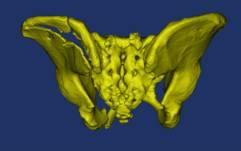

骨盆术前三维模型和模拟复位--正位后面观